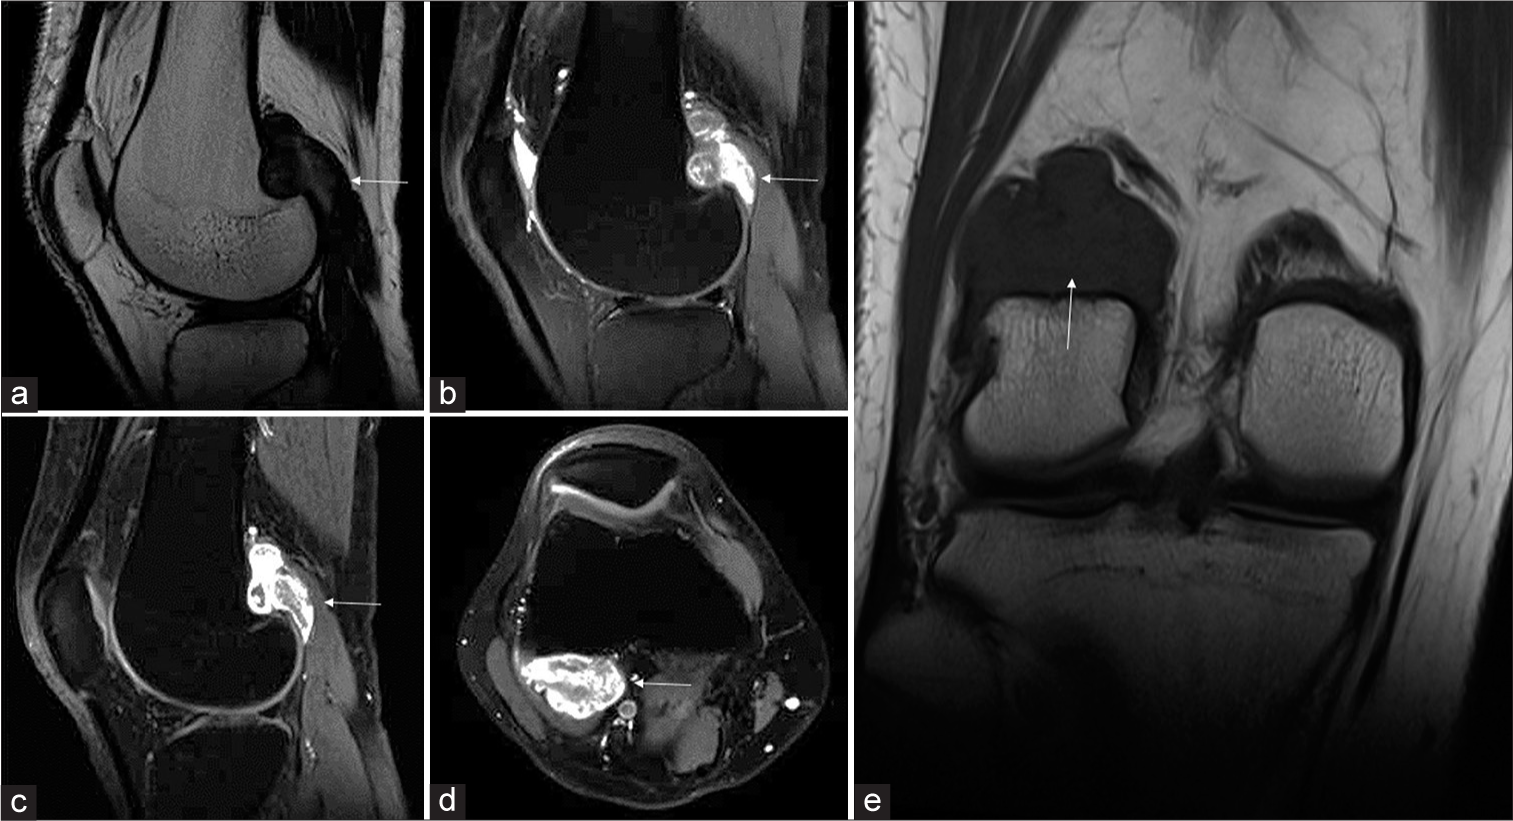

🧲 Resonancia magnética (RM)

La RM es la prueba de elección cuando existen dudas diagnósticas. Permite confirmar la naturaleza fibrosa de la lesión y descartar signos de agresividad. Los hallazgos característicos son:

| Secuencia | Hallazgo típico | Significado |

|---|---|---|

| T1 | Señal intermedia / hipointensa | Compatible con tejido fibroso. |

| T2 / STIR | Predominio hipointenso con posible ribete periférico de edema | La hipointensidad predominante en T2 es característica del colágeno denso y la fibrosis madura. |

| Post-contraste | Realce leve a moderado, variable | Sin patrón agresivo ni componente blando dominante. |

Figura. RM de tumor desmoide periostal de rodilla con scalloping liso del cóndilo femoral lateral. Imagen tomada de Handa S, Prajapati T, Phulware RH, Saran S. Indian Journal of Musculoskeletal Radiology, 2025. Licencia CC BY-NC-SA 4.0.

Corrección importante: lo característico en T2 es la hipointensidad predominante (señal baja) por el tejido fibroso. Si un informe describe “hiperintensidad en T2”, probablemente se refiere a edema perilesional o a otra entidad.